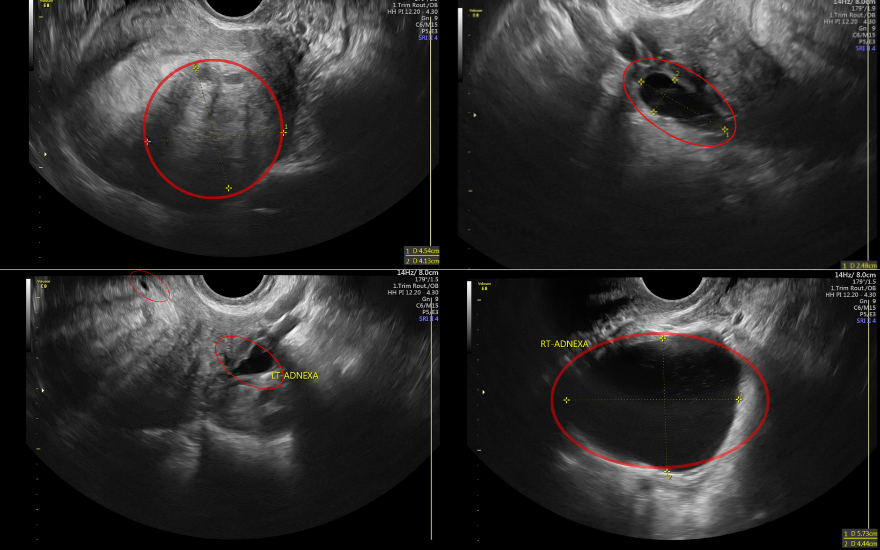

Khi các cơn đau kéo dài và ngày càng trầm trọng, chị H mới quyết định đến BVĐK Hồng Ngọc Phúc Trường Minh thăm khám. Qua siêu âm, các bác sĩ phát hiện bệnh nhân có khối lạc nội mạc tử cung kích thước khoảng 5cm, kèm theo nhiều tổn thương nhỏ ở buồng trứng và thành bụng, đây chính là nguyên nhân khiến tử cung và buồng trứng bị chèn ép, gây đau dai dẳng, thậm chí có thể biến chứng nguy hiểm nếu không xử trí kịp thời.

Siêu âm cho thấy chị H có nhiều khối lạc nội mạc cùng các nang buồng trứng.